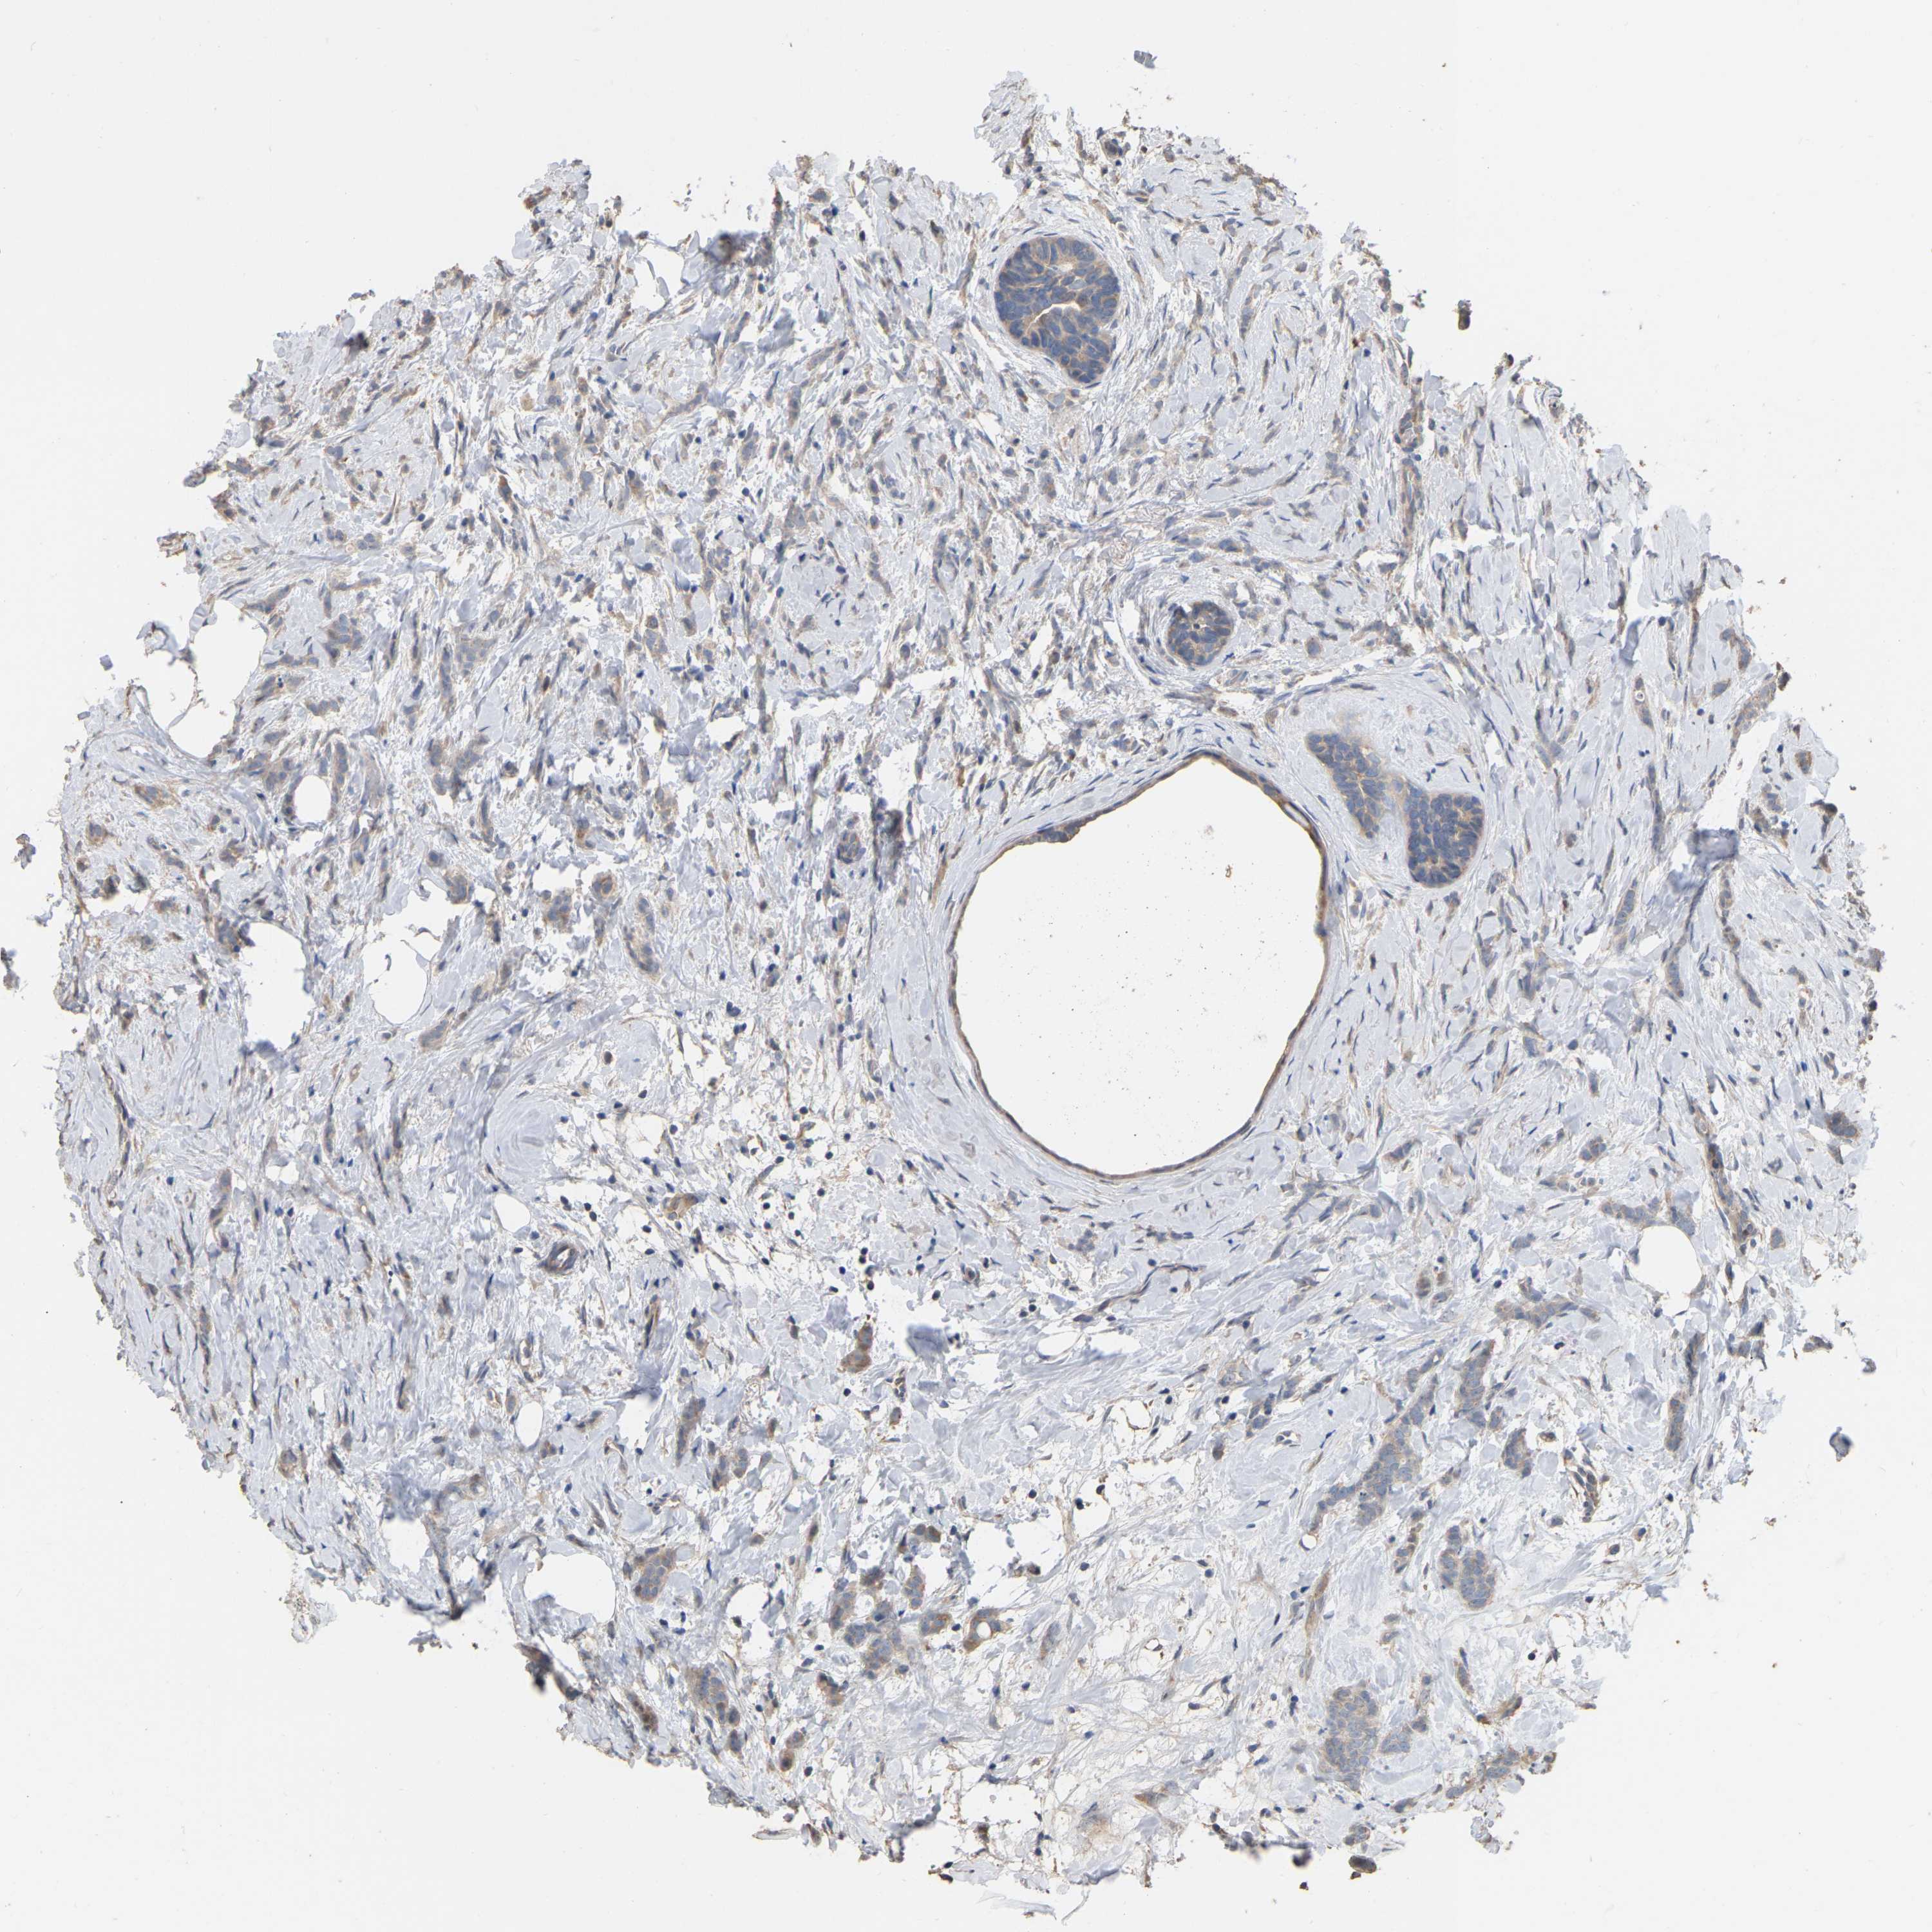

CANCER BREAST CANCER Show tissue menu

BRCA TCGA BRCA VALIDATION PROTEIN EXPRESSION